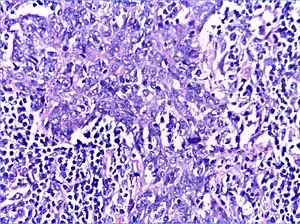

Histology

There is a marked lymphoplasmacytic infiltration. Lymphoid follicles surround solid epithelial nests, giving rise to the 'epimyoepithelial islands', that are mainly composed of ductal cells with occasional myoepithelial cells. Excess hyaline basement membrane material is deposited between cells, and there is also acinar atrophy and destruction.